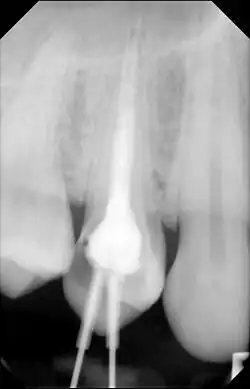

Leczenie kanałowe, leczenie endodontyczne, endodoncja – metoda leczenia nieodwracalnych zapaleń miazgi zęba. Polega na usunięciu (w znieczuleniu) chorobowo zmienionej miazgi z komory i kanałów zęba, zdezynfekowaniu ich i wypełnieniu odpowiednim materiałem, najczęściej gutaperką. Całe leczenie powinno odbywać się pod kontrolą radiologiczną, a w niektórych przypadkach w powiększeniu (pod mikroskopem operacyjnym).

Prawidłowo wyleczony ząb pozostaje w jamie ustnej bardzo długo i nie daje żadnych objawów niepożądanych. Efekt leczenia w postaci cofających się zmian pod zębem widać już po pół roku od zakończenia leczenia na zdjęciu rentgenowskim.

Najczęściej stosowanym narzędziem obrazowania w endodoncji jest rentegenografika tradycyjny (RTG). Umożliwia zobrazowanie liczby kanałów korzeniowych i ich układu w zębie. Pozwala to na identyfikację anatomii korzeniowej. Można ocenić, czy ząb ma jeden czy wiele kanałów, oraz jak są one rozmieszczone. Ponadto, rentgenografika pozwala na ocenę stanu kości wokół wierzchołka korzenia. To pomaga w identyfikacji obszarów resorpcji kości, zmian zapalnych, czy obecności ropni. Może to sugerować obecność infekcji lub przewlekłego zapalenia[1].

- Wypełnienie kanałów materiałami biozgodnymi. Czynność ta ma na celu szczelne zamknięcie światła kanału na całej długości do otworu fizjologicznego, aby uniemożliwić przenikanie bakterii z jamy zęba do tkanek okołowierzchołkowych. Wypełnianie kanałów korzeniowych wymaga zastosowania różnych materiałów i technik. Materiały wypełniające możemy podzielić na stosowane czasowo i stosowane na stałe do ostatecznego wypełnienia. Najpopularniejszym materiałem do wypełniania kanałów korzeniowych na stałe jest gutaperka, która stosowana od blisko 100 lat, mimo wielu nowych materiałów, jest najlepszym wypełniaczem kanałów, dającym doskonałe efekty lecznicze.